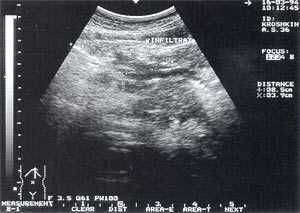

- увеличение размеров поджелудочной железы (рис. 1) - отмечено в 88% случаев. Нормальные размеры поджелудочной железы: головка 3-4,5 см; тело 2,5 - 3 см; хвост 3-4 см;

- увеличение расстояния между задней стенкой желудка и передней поверхностью поджелудочной железы свыше 3 мм и достигающее 10 - 20 мм, что характеризует отек парапанкреатических тканей, отмечено в 53% наблюдений (рис. 1);

Рис. 1. Острый панкреатит, деструктивная форма. Увеличение размеров поджелудочной железы, нечеткость контуров, увеличение расстояния между задней стенкой желудка и поджелудочной железы.